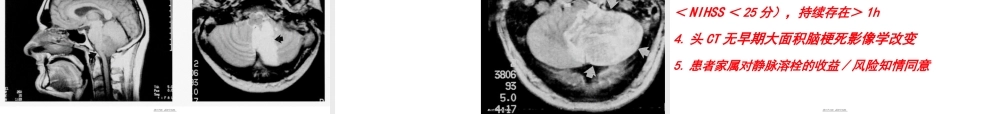

1急性(jíxìng)脑梗塞及溶栓治疗单晓琳内分泌一科第一页,共五十五页。第一页,共五十五页。•溶栓安全吗?•应该溶栓吗?•使用什么药物溶栓?•药物剂量如何?•如何临床管理?•如何监测(jiāncè)?如何护理?•如果不进行溶栓治疗会怎样?第二页,共五十五页。第二页,共五十五页。•缺血半暗带的形成、演变和临床意义急性脑梗死病灶是由中心坏死区及其周围的缺血半暗带(ischemicPenumbra)组成。急性脑梗死发生后,在中心坏死区的周围形成缺血半暗带。缺血半暗带内仍有侧支循环存在,可获得部分血液供给,尚有大量可存活的神经元。如果血流迅速恢复,损伤是可逆的,脑代谢障碍可恢复,神经细胞仍可存活并恢复功能。保护缺血半暗带区的神经元是急性脑梗死治疗(zhìliáo)成功的关键。第三页,共五十五页。第三页,共五十五页。缺血半暗带(可逆性脑损伤)GonzálezRG.AJNRAmJNeuroradiol.2006Apr;27(4):728-35.SaverJF.Stroke2006;37:263-266.未治疗(zhìliáo)的缺血性脑卒中患者,缺血区每分钟将有190万个神经元死亡10早期溶栓再灌注(guànzhù)治疗,有利于挽救可逆性脑损伤9缺血中心区(不可逆性脑损伤)第四页,共五十五页。第四页,共五十五页。•静脉溶栓•动脉溶栓•动静脉联合(liánhé)溶栓•机械溶栓第五页,共五十五页。第五页,共五十五页。•前循环静脉(jìngmài)内溶栓的时间窗为3小时动脉内溶栓的时间窗为6小时•后循环静脉或动脉的溶栓时间窗可达12小时第六页,共五十五页。第六页,共五十五页。发病(fābìng)时间发病时间:是患者最后看起来正常状态的时候为发病时间,而不是症状(zhèngzhuàng)出现时间7第七页,共五十五页。第七页,共五十五页。异常灌注的区域(qūyù)可以是坏死组织或存在坏死风险的组织结合弥散及灌注影像可以帮助我们确认那些存在坏死风险的组织,亦即所谓的缺血半影区第八页,共五十五页。第八页,共五十五页。在左侧首先(shǒuxiān)一个DWI显示一个不可逆的坏死中间图像显示灌注不足的范围更大右侧是弥散-灌注的结合像蓝色显示缺血半影区,这些组织是可以通过治疗获得恢复的Diffusioninyellow.Perfusioninred.Mismatchinblueispenumbra.第九页,共五十五页。第九页,共五十五页。发病一小时(xiǎoshí)后行MR扫描,你发现了什么?第十页,共五十五页。第十页,共五十五页。DWI序列上显示一个右侧大脑中动脉供血区的广泛的弥散受阻基底节同时(tóngshí)受累弥散成像病变范围与DW...